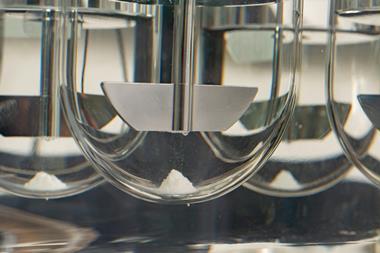

Recent authorisation of Inlexzo ™ (gemcitabine intravesical system) by the US Food and Drug Administration (FDA) offers certain patients with Bacillus Calmette-Guérin (BCG)-unresponsive non-muscle invasive bladder cancer (NMIBC) a novel treatment alternative.

It is indicated for NMIBC patients with carcinoma in situ (CIS), with or without papillary tumours, and for individuals who have limited options prior to possible bladder removal.

Inlexzo (previously known as TAR-200), remains in the bladder for three weeks per treatment cycle for up to 14 cycles.

- Formulation and drug delivery